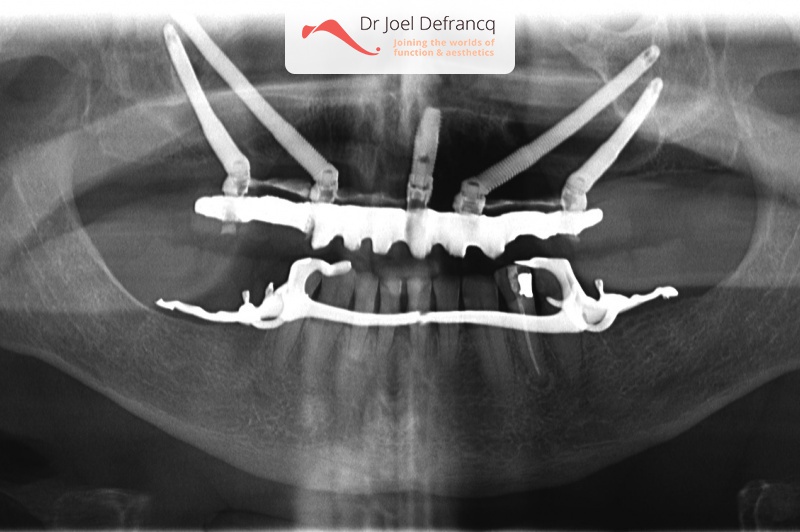

Maurice

Behandeling tandheelkundige implantaten

- Zygoma implantaten